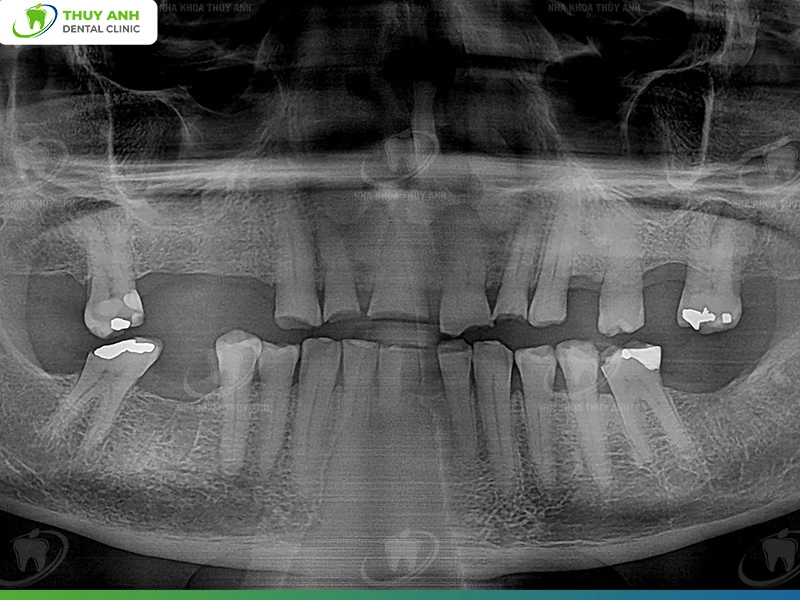

For many years, he suffered from severe bruxism (teeth grinding). Over time, this condition led to progressive tooth wear:

- Many teeth were worn deeply into dentin, approaching the pulp

- Several teeth were severely fractured and lacked sufficient clinical crown height

- Multiple posterior teeth were missing

Examination and Detailed Treatment Planning

During the first visit, Philip underwent a comprehensive assessment, including:

- Clinical intraoral examination and evaluation of each tooth

- Panoramic X-ray

- Cone Beam CT scan

This data allowed clinicians to accurately assess:

- Bone volume and density

- The position of critical anatomical structures (inferior alveolar nerve, mental nerve, maxillary sinus)

- The condition of remaining teeth

- The degree of vertical dimension loss due to tooth wear